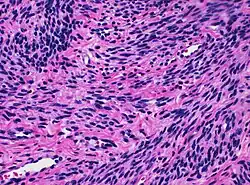

Histology of myometrium

The myometrium is the middle layer of the uterine wall, consisting mainly of uterine smooth muscle cells (also called uterine myocytes[1]) but also of supporting stromal and vascular tissue.[2] Its main function is to induce uterine contractions.

The myometrium is located between the endometrium (the inner layer of the uterine wall) and the serosa or perimetrium (the outer uterine layer).